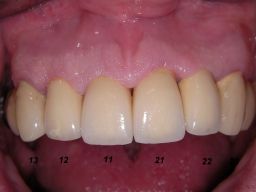

Am 28.2.06 erfolgte die endgültige Präparation (das "Beschleifen") aller 4 Zähne. Links das Modell, auf dem die Kronen gefertigt worden waren. Rechts kurz vorm Zementieren der Kronen am 13.3.06. Aus der Längendifferenz der Zähne rechts und links kann man darauf schließen, daß die Präparation tief unter dem Zahnfleisch erfolgen mußte. |

Links die Kronen aus dem Dentallabor "Heitmeyer Zahntechnik", Osnabrück. Man sieht praktisch keinen Metallrand. Der Patient war zur Farbbestimmung im Dentallabor - so halten wir es praktisch immer. Rechts das Ergebnis bei der 1. Nachkontrolle am 27.3.05. Das Zahnfleisch muß sich noch etwas erholen. |